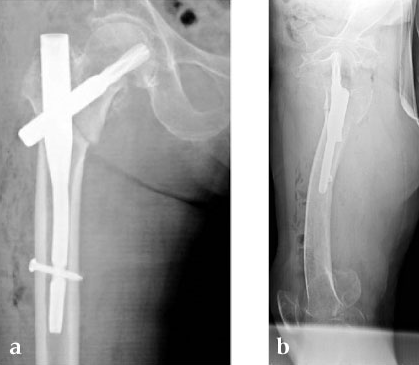

A 78-year-old Japanese patient fell while at her home and sustained an AO 31-A2.1 injury (see Fig 5).

She was operated on the next day and fixed with a PFNA Asia (size: extra small, angle 130 degrees, distal diameter: 9 mm, blade length 100 mm) (Fig 6a). Good reduction and stable fixation were obtained. Full weight-bearing gait was allowed on the second postoperative day. There was an uneventful postoperative course, and good union was obtained at three months after surgery (Fig 6b).